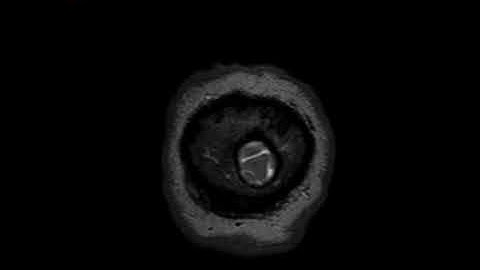

AE036 | MRI Image Based Brain Tumor Detection Using CNN | Blockchain